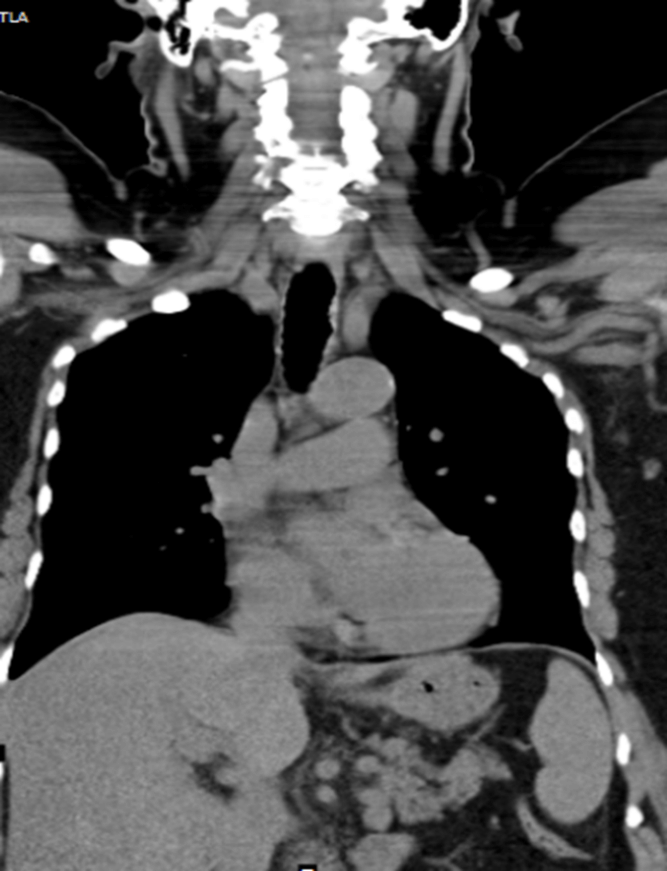

Contrast enhanced computed tomography (CECT) of neck and thorax reported intraluminal mildly enhancing polypoidal mass lesion measuring 2.58 x 1.54 x 1.51 cm (Cc X AP X Tr) in the upper trachea at the level of C6, C7 vertebral body. Significant luminal compromise was noted at the level of the mass lesion. Rest of the lung parenchyma was unremarkable. Flexible bronchoscopy examination revealed a large polyploidal growth approximately 3 cm from the vocal cords. The growth was moving with respiration and causing critical airway narrowing at the upper trachea (approximately 80%).

CECT at presentation: Intraluminal mass lesion in the upper trachea

CECT at presentation

There were no intra-operative and post-operative procedural complications. Histopathology of the tumour was reported as squamous cell carcinoma. Repeat CT post procedure revealed complete patency of the tracheal lumen with mild wall thickening and irregularity. The patient is being treated with External Beam radiation therapy by the oncology team.